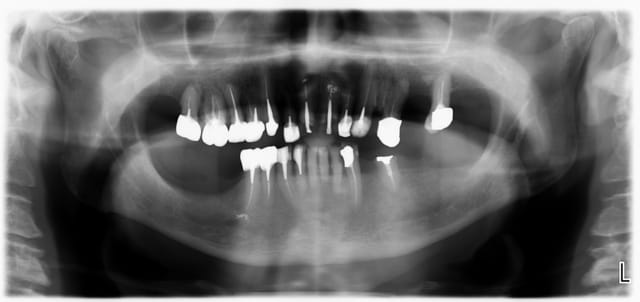

Ca c'est un boulot qui m'a fait extrêmement plaisir, parce que je trouve qu'on touche là à l'essence même de notre activité: permettre aux gens de manger.

Ce monsieur, 80 piges au compteur, est arrivé avec des vieilles provisoires, des gros compos, tout se cassait la figure... "Oh, mais à mon âge est-ce que ça vaut bien le coup de mettre des sous dans les dents..."

Pas de vraies difficultés techniques, pas de recherche esthétique marquée, du métal, on a reconstruit une occlusion de 5 à 5 seulement. Mais niveau qualité de vie, j'aimerai être toujours aussi efficace.

Photos un an après la pose. Pano avant.